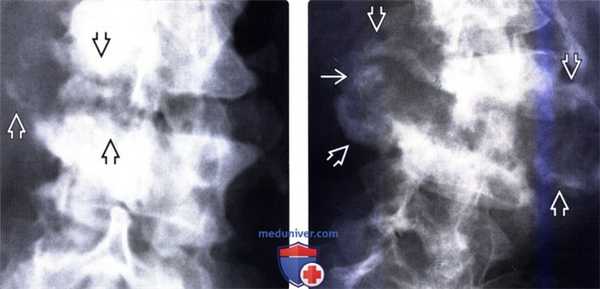

(Слева) Рентгенограмма в прямой проекции: ранние проявления нейрогенной артропатии. Ключом к диагнозу служат фокальные деструктивные изменения замыкательных пластинок и наличие костного дебриса. При инфекционном процессе обычно наблюдается более равномерное поражение замыкательных пластинок и отмечается тенденция к остеопении.

(Справа) На рентгенограмме в прямой проекции у этого же пациента, выполненной два месяца спустя, отмечается быстрое прогрессирование нейрогенной артропатии. Обратите внимание на сформировавшуюся скол иотическую деформацию и подвывих позвонка, массивные спондилофиты, костный дебрис и признаки деструкции костной ткани на уровне межтелового пространства.